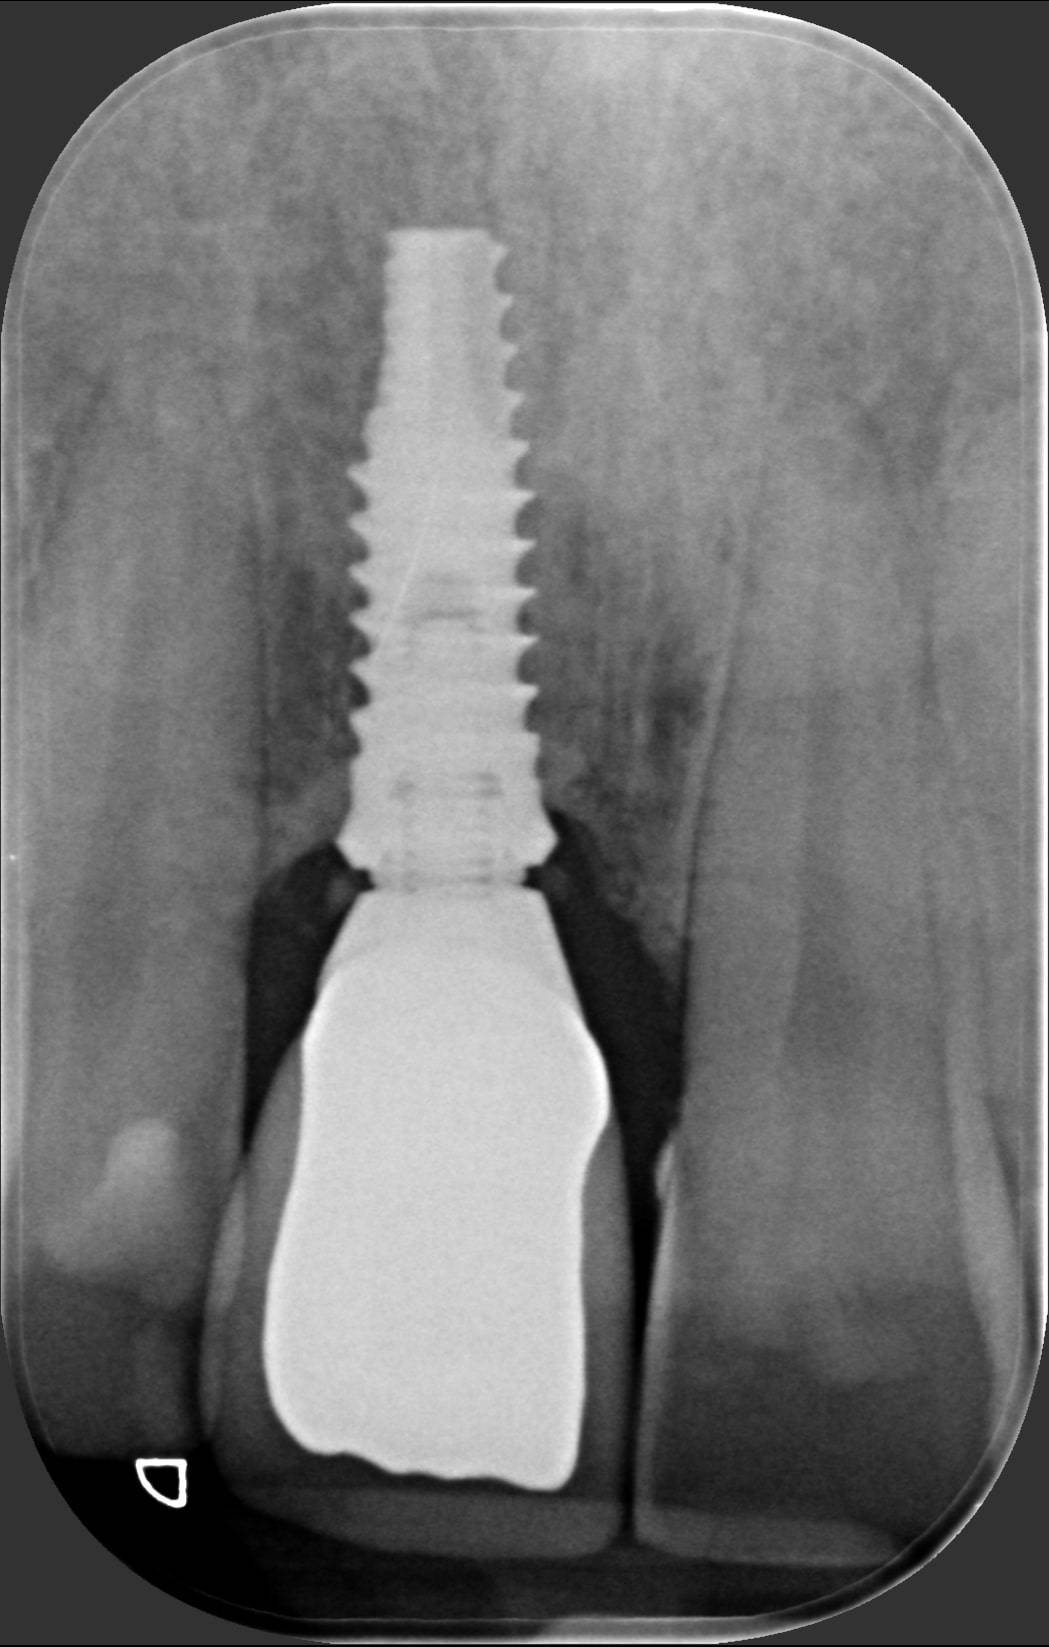

Indovina dov'è l'impianto, memory game

Ti sembra tutto normale in questa foto? Incisivi allineati e con un bel colore chiaro, gengive perfette e assolutamente non infiammate. E se invece ti dicessi che uno di questi denti è un impianto? Su quale scommetteresti? Ti sei mai fatto dei problemi a scoprire i denti quando ridi? Alle volte una caduta accidentale o un trauma durante un’attività sportiva possono toglierti la voglia di ridere liberamente. Guarda la foto successiva e capirai. A questo punto cosa potrebbe capitare? Inizi a sorridere con le labbra sigillate perché ti vergogni del tuo “buco” mentre ridi e ti diverti in compagnia. Questo giovane ragazzo ha perso l’incisivo centrale durante una partita di calcio fra amici. Aveva addirittura perso la parte esterna dell’osso che lo teneva in posizione. Ho dovuto mettergli un impianto osteointegrato e fare quello che noi dentisti chiamiamo “rigenerazione ossea guidata” per ricostruirgli l’estetica naturale che vedi nella prima foto. Solo nella terza puoi vedere cosa c’è dentro, al posto del suo dente ormai perso. La cosa bella è che non è mai stato senza il suo dente, nemmeno per un giorno. Premesso che è sempre meglio curare e salvare i propri denti, quando li devo sostituire, puoi contare sull’efficacia e sull’aspetto naturale degli impianti dentali. Questo ed altro è quello che facciamo nello Studio dentistico del dott. Fabio Ballestrasse a Besana Brianza (MB) e se sei di Verano Brianza, puoi raggiungerci facilmente.